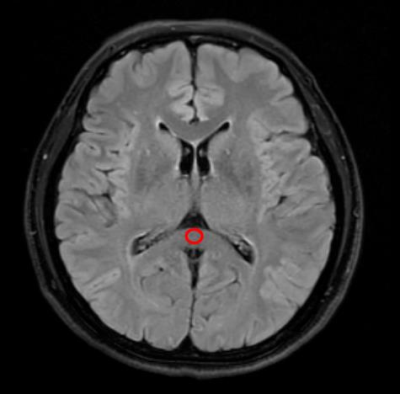

Figure 2 T2-FLAIR image of a 55 years old female. This figure shows an example of ROI at corpus callosum which was used to calculate SNR and CNR.